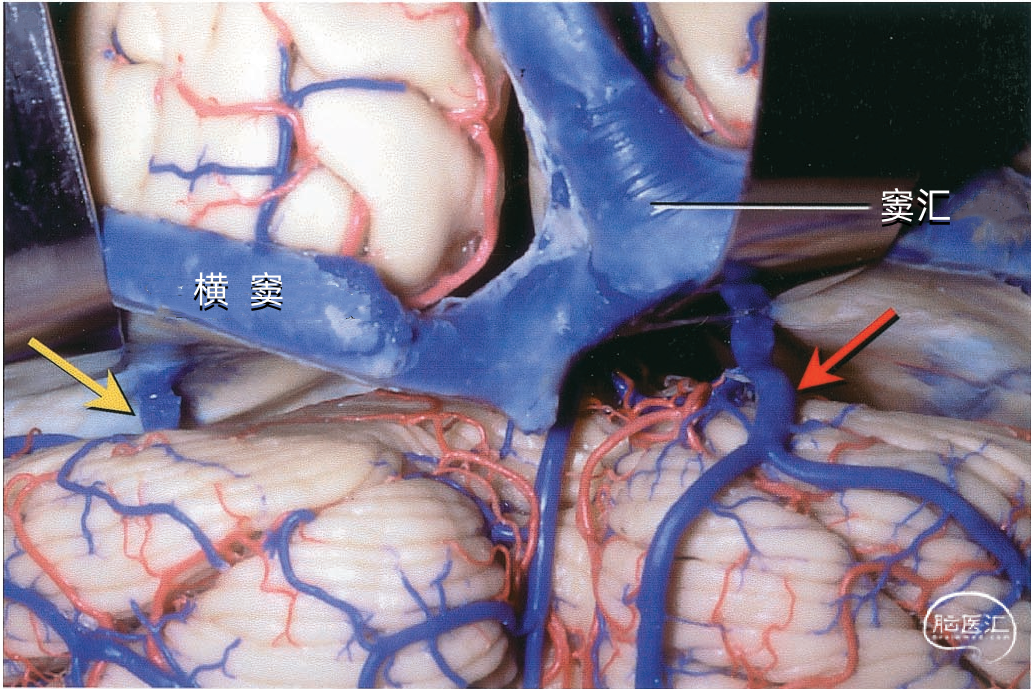

窦汇(confluence of sinuses)位于枕内隆凸平面,正中线稍偏右侧,相当于人字缝尖至枕骨大孔后唇的中点处。通常由上矢状窦与直窦在枕内隆凸处汇合而成。向左、右两侧汇入横窦。 上矢状窦和直窦的汇合方式颇多,窦汇的延续情况也各有差异。上矢状窦、直窦汇入右侧横窦者较多,约占30%。上矢状窦和直窦各分为左右支,两窦的右支合为右横窦,两窦的左支合为左横窦者占26%。而上矢状窦、直窦、枕窦及横窦汇合者占22%。▼8.横窦

横窦(transverse sinus)从枕内隆凸沿小脑幕在枕骨内侧面附着形成的浅沟向外侧走行。在岩骨嵴后方,横窦和岩上窦汇合处,横窦离开小脑幕,转向下前方,移行于乙状窦。横窦除主要收纳上矢状窦和直窦的血液外,还收纳大脑下静脉、小脑下静脉、脑干静脉、板障静脉和导静脉的血液。横窦可通过枕骨的导静脉与颅外静脉相通。 横窦于枕内隆凸附近的起点变化颇多,可以起自窦汇,也可起自上矢状窦或直窦(上图)。 上矢状窦可平均回流入左右两侧横窦,或一侧为主,或完全一侧。 右侧横窦通常较大,并接受上矢状窦的大部分引流(上图)。左侧横窦较小,主要接受直窦引流。所以,右侧的横窦、乙状窦和颈内静脉的血液主要来自大脑的浅部结构,左侧的横窦、乙状窦和颈内静脉内的血液主要来自大脑内静脉、基底静脉和大脑大静脉引流的深部结构。每侧的引流差异导致一侧或另一侧静脉回流受阻产生不同的临床症状,且左侧或右侧颈内静脉压迫产生不同的Queckenstedt's奎肯征。

每侧小脑幕有两个恒定但不对称的静脉窦,即内侧小脑幕窦和外侧小脑幕窦。 内侧小脑幕窦由小脑上表面的回流静脉汇聚而成。内侧小脑幕窦向内侧引流入直窦,或直窦与横窦的汇合处。 外侧小脑幕窦由颞叶和枕叶基底面和外侧面的回流静脉汇聚而成。外侧小脑幕窦起自小脑幕的外侧部分,并向外侧引流入横窦的末端。 下图示抬起小脑幕,可见来自小脑、在小脑幕下缘入窦的桥静脉。左侧黄色箭头显示一支较大的静脉自小脑上表面进入内侧小脑幕窦。右侧红色箭头显示一支粗大的来自小脑上表面的桥静脉在窦汇前方进入内侧小脑幕窦。

下图示汇入外侧小脑幕窦的颞底静脉、枕底静脉。左侧红色箭头指示左侧汇入小脑幕窦属支的颞底长静脉。颞底静脉汇入有多个属支的小脑幕窦。右侧黄色箭头显示汇入右侧小脑幕窦的静脉属支。 下图示(左侧)颞底静脉和枕底静脉汇聚于两个横窦内侧的短小脑幕窦。(右侧)Labbé静脉和颞后静脉直接引流入横窦。左侧小脑幕的另一个窦(小脑幕内侧窦)(黄色箭头)接受来自小脑的引流,向内侧经过小脑幕汇入窦汇。